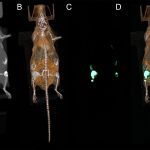

ScanNanoTreat is an EIC Transition project developing a breakthrough theranostic platform that combines next-generation Spectral Photon Counting CT (SPCCT) with X-ray-activated Photodynamic Therapy (X-PDT). This integrated system is engineered to image and treat solid tumours in a single workflow, bringing unprecedented speed, precision, and safety to cancer care.

• Spectral Photon Counting CT (SPCCT)

Delivering high-resolution, low-energy imaging with unprecedented material differentiation.

• X-ray-activated Photodynamic Therapy (X-PDT)

Triggered by innovative gadolinium-based nanoprobes, enabling targeted, minimally invasive tumour damage.